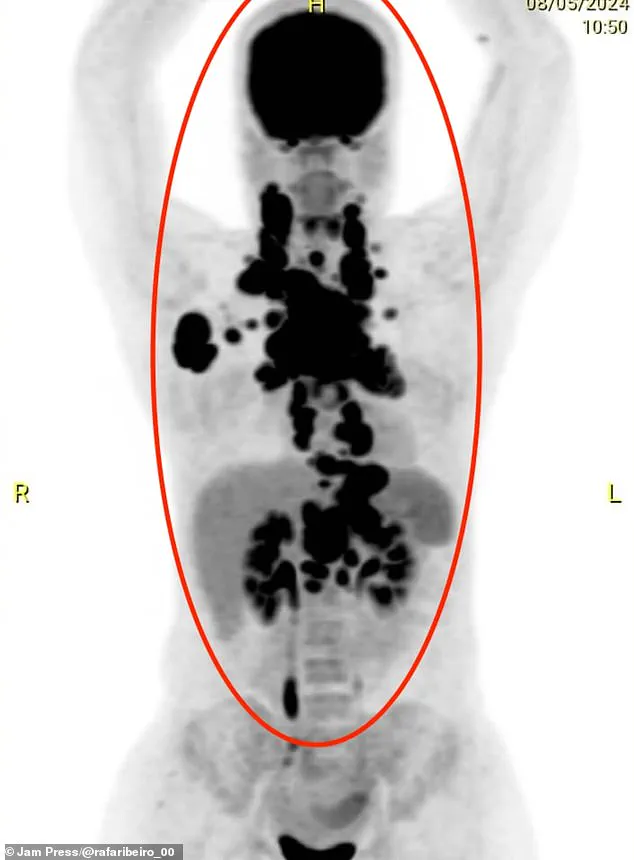

At first, medics dismissed Ms Ribeiro’s symptoms as pneumonia or an allergic cough, but after she collapsed and could no longer eat, scans revealed that her upper body was packed full of tumours.

She said: ‘The tumours were crushing me from the inside.

My oesophagus was compressed, and my heart felt like it was being taken over, but it was just the pressure from the tumours.’

This x-ray shows how tumours were ‘crushing’ her internal organs.